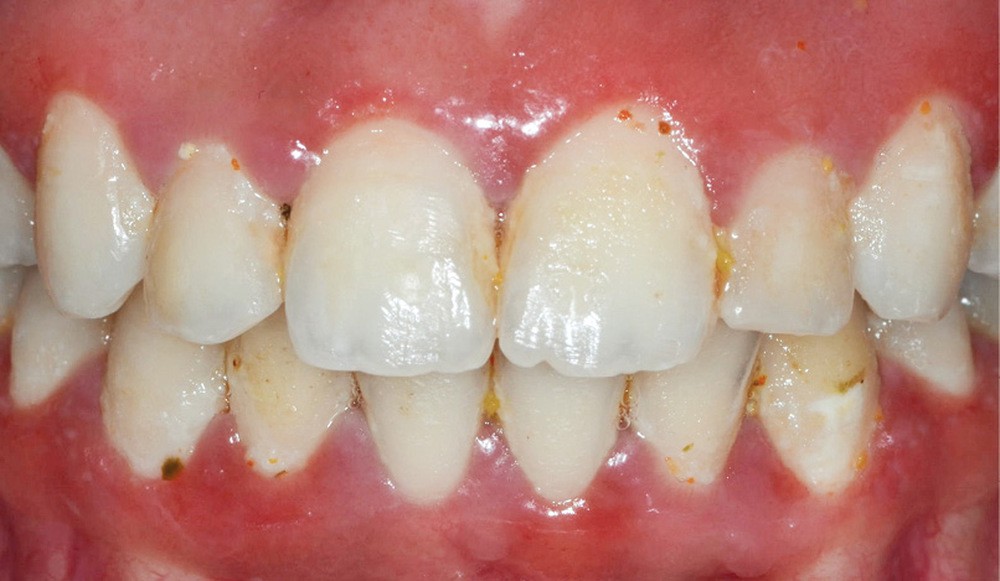

Les dyschromies extrinsèques

Elles sont causées par des agents colorants externes qui se déposent généralement sur la surface amélaire. Leurs origines sont diverses : alimentation (fig. 1b), tabac (fig. 1c), plaque bactérienne ou bactéries chromogènes (fig. 1d), ainsi que certains médicaments. La réalisation d’un aéropolissage en complément du détartrage initial est généralement suffisante pour éliminer efficacement ces colorations. Cependant, le patient doit être prévenu qu’en l’absence de modification de ses habitudes de vie, celles-ci reviendront [2, 4].